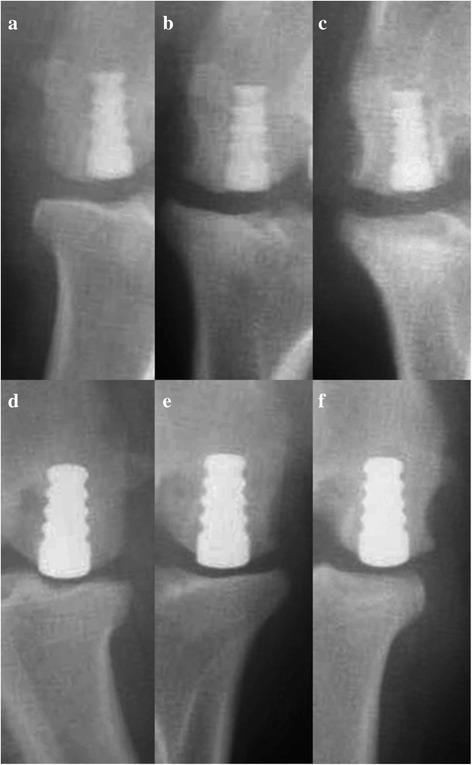

METHODS

A canine model (n = 9) was used to evaluate the in vivo histologic response and function of a pyrolytic carbon implant replacing a full-thickness osteochondral defect in the medial femoral condyle (MFC) of the knee. The gross appearance and histologic results were compared to an identical cobalt-chromium (Co-Cr) alloy implant placed in a defect in the contralateral MFC and evaluated up to 52 weeks.

两种植入物类型均观察到骨与柄部的广泛融合。在所有评估期,与Co-Cr合金植入物相比,热解碳植入物周围MFC软骨的总平均组织学评分均有显著改善(p < 0.05)。热解碳植入物在52周时的组织学分级和大体观察结果与Co-Cr合金植入物在24周时相似。在24周时,Co-Cr合金植入物的总平均组织学评分为11.6 ± 0.7(0 - 16分范围;16 = 正常外观),而在52周时,热解碳植入物的总平均评分为11.7 ± 1.3。在所有评估期,热解碳植入物相对的内侧胫骨软骨的总平均组织学评分均优于Co-Cr合金组,且在24周(p = 0.001)和52周(p < 0.001)时显著优于Co-Cr合金植入物组。

结论

与相同的Co-Cr合金植入物相比,使用热解碳植入物重建局灶性软骨缺损显示出有效的植入物固定和更好的体内反应。